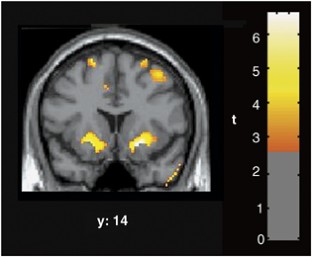

Changes in brain function during the initial weeks of abstinence from chronic methamphetamine abuse may substantially affect clinical outcome, but are not well understood. We used positron emission tomography with [F-18]fluorodeoxyglucose (FDG) to quantify regional cerebral glucose metabolism, an index of brain function, during performance of a vigilance task. A total of 10 methamphetamine-dependent subjects were tested after 5–9 days of abstinence, and after 4 additional weeks of supervised abstinence. A total of 12 healthy control subjects were tested at corresponding times. Global glucose metabolism increased between tests (P=0.01), more in methamphetamine-dependent (10.9%, P=0.02) than control subjects (1.9%, NS). Glucose metabolism did not change in subcortical regions of methamphetamine-dependent subjects, but increased in neocortex, with maximal increase (>20%) in parietal regions. Changes in reaction time and self-reports of negative affect varied more in methamphetamine-dependent than in control subjects, and correlated both with the increase in parietal glucose metabolism, and decrease in relative activity (after scaling to the global mean) in some regions. A robust relationship between change in self-reports of depressive symptoms and relative activity in the ventral striatum may have great relevance to treatment success because of the role of this region in drug abuse-related behaviors. Shifts in cortical–subcortical metabolic balance either reflect new processes that occur during early abstinence, or the unmasking of effects of chronic methamphetamine abuse that are obscured by suppression of cortical glucose metabolism that continues for at least 5–9 days after cessation of methamphetamine self-administration.